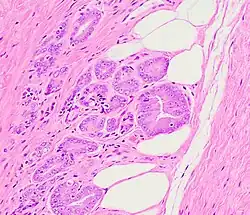

Usually, the grade of the cancer (how different the tissue is from normal tissue) is evaluated separately from the stage. For prostate cancer, cell morphology is graded based on the Gleason grading system.

Of note, this system of describing tumors as "well-", "moderately-", and "poorly-" differentiated based on Gleason score of 2–4, 5–6, and 7–10, respectively, persists in SEER and other databases but is generally outdated. In recent years pathologists rarely assign a tumor a grade less than 3, particularly in biopsy tissue.

- ^ Image by Mikael Häggström, MD. Reference for implication: Grignon DJ (2018). "Prostate cancer reporting and staging: needle biopsy and radical prostatectomy specimens". Mod Pathol. 31 (S1): S96-109. doi:10.1038/modpathol.2017.167. PMID 29297497. Archived from the original on June 14, 2024.

- ^ Image by Mikael Häggström, MD. Reference for implication: Ye H, Walsh PC, Epstein JI (2010). "Skeletal muscle involvement by limited Gleason score 6 adenocarcinoma of the prostate on needle biopsy is not associated with adverse findings at radical prostatectomy". J Urol. 184 (6): 2308–12. doi:10.1016/j.juro.2010.08.006. PMID 20952012. Archived from the original on July 13, 2025.